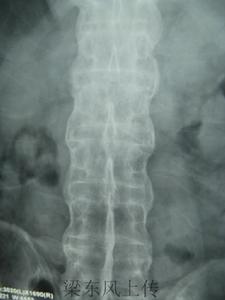

脊柱的X線片表現有椎體骨質疏鬆和方形變,椎小關節模糊,椎旁韌帶鈣化以及骨橋形成。晚期廣泛而嚴重的骨化性骨橋表現稱為“竹節樣脊柱”,見圖4。恥骨聯合、坐骨結節和肌腱附著點(如跟骨)的骨質糜爛,伴鄰近骨質的反應性硬化及絨毛狀改變,可出現新骨形成,這些主要是附著點炎的放射學表現,和骶髂關節炎可以(或不)同時出現於脊柱關節炎患者。